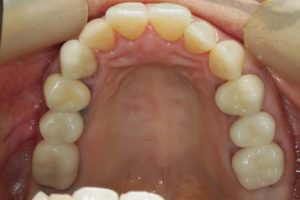

どのように変わったか、下の写真をご覧ください。

銀歯が多かったのですべて昔の銀歯の下もちりょうしながらセラミックにかえることができてとても満足しています。やっぱり白い歯よいですね。

治療お疲れ様でした。たくさん銀歯が入っていたのですが、最後には真っ白になりましたね。銀歯をやり直す材料にはセラミックとプラスティックがあるのですが、基本的にできるだけプラスティックで治すようにしています。この患者さんも、可能な限りプラスティックで治し、どうしても無理なところだけセラミックにしました。そのため歯を削る量が少ないことに加え、費用もかなり抑えることができます。たくさん治しましたが、全部セラミックで治さなければならないとなっていたら、もっともっと時間も費用もかかっていたかもしれません。当院では、初診時に治療方針や期間や費用などを1時間ほどかけて詳しく説明していますので、患者さんには治療内容について十分納得していただいていると考えています。「親身になって治療してくれる」とおっしゃっていただいたことは、そういったところを評価して頂いたのではいかと思っております。